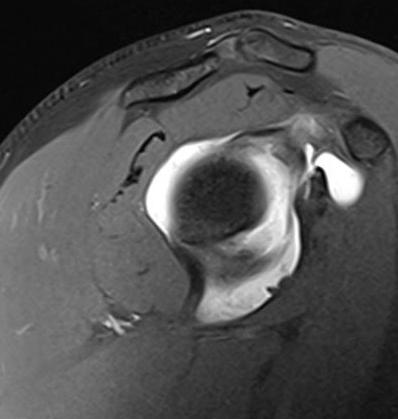

Artroresonancia magnética de hombro derecho con resonador de 1.5T. Se inyectaron 15cc de medio de contraste intraarticular bajo guía ecográfica en el receso articular posterior, obteniendo imágenes multiplanares en secuencias T1-FS, DP-FS y volumétricas T2-me3D.

Figura 1: Secuencia sagital T1-FS: adecuada distensión de la cápsula articular tras la administración directa de medio de contraste bajo guía ecográfica.

Subluxación posterior de la cabeza humeral con condrosis grado 4 y cuerpo libre osteocondral en el espacio subcoracoideo.